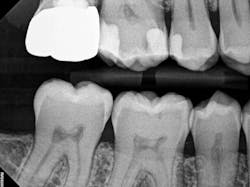

The iTero scanner was able to clearly define the delineation between the soft and hard tissue as can be seen in this image of the digital die trim (figure 3). Radiographs were captured on delivery revealing a clinically acceptable outcome for the patient (figure 4). Direct restorations were completed on teeth Nos. 3 and 4 during this visit.